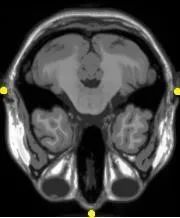

多模配准常见于医学图像领域,故以多模医学图像配准为例。

由于医学成像设备可以提供关于患者不同信息不同形式的图像(计算机断层扫描CT,核磁共振MRI,正电子发射断层成像PET,功能核磁共振fMRI等)。

基于单种或多种模态图像的配准,可划分为单模态(Single-modality)和多模态(Multi-modality)。

MEG-MRI多模态配准